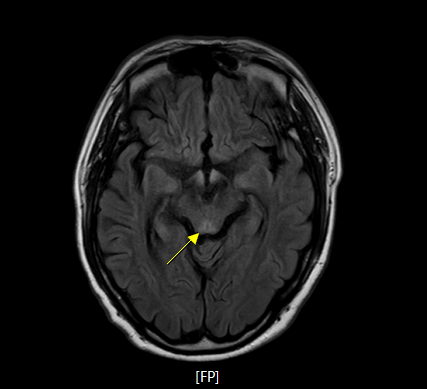

- 뇌 MRI(brain MRI) 영상은 T2 flair 및 brain DWI 영상에서 아래와 같은 영역에서 양측성 signal intensity의 증가 소견을 보이게 된다.

- mammillary body

- dorsomedial thalami

- tectal plate

- periaqueductal grey matter

- around the third ventricle

- cerebral cortex

- 급성 베르니케 뇌병증의 병변은 vascular congestion(혈관 충혈), microglial proliferation(뇌 대식세포의 증식), petechial hemorrhage(점상 출혈)에 의해서 발생하며, 만성적으로는 demyelination(탈수초화), gliosis, neuropil의 소실로 이어지게 된다. 신경의 소실은 상대적으로 medial thalamus에서 현저히 발견되고, mamillary body의 위축은 베르니케 뇌병증, 코르사코프 증후군의 환자 최대 80%에서 확인되고 있다.

- 흔히 병변이 확인되는 구조물 : the 3rd ventricle, aqueduct, fourth ventricle, dorsomedial thalamus, locus ceruleus, peri-aqueductal gray, ocular motor nuclei, vestibular nuclei, fornices, septal region, hippocampus, cerebral cortex 등에서 보이며, 주로는 대칭적으로 확인된다.